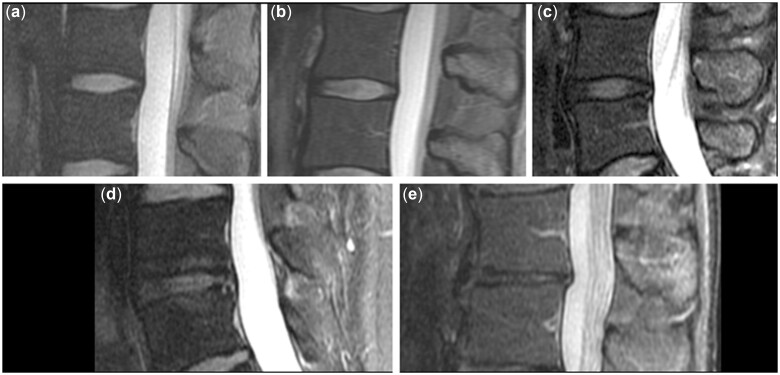

Modic-type endplate changes summarize three categories based on specific signal characteristics of vertebral BM adjacent to the endplates in MRI [23]. Most commonly, type 1 changes are considered an inflammatory, fibrovascular stage and may indicate an ongoing active degenerative process (e.g., disruption and fissuring of endplates and formation of granulation tissue) [23, 24]. Type 2 changes are related to fatty degenerative remodeling processes, with replacement of red by yellow BM within the vertebrae [23, 24]. Furthermore, type 3 changes reflect the sclerotic stage [23, 24]. Related to their suggested pathophysiological entity, the three different types of Modic-type endplate changes differ in their appearances using the combination of sagittal T1- and T2-weighted sequences, with Modic changes type 1 typically showing hypointense signal on T1- and hyperintense signal on T2-weighted images, Modic changes type 2 showing hyperintense signal on T1- and hyper- or iso-intense signal on T2-weighted images without FS (typically relatively hypointense on T2-weighted images with FS), and Modic changes type 3 showing hypointense signal on T1- and T2-weighted images [23, 25, 26]. However, mixed types can be observed frequently for one lumbar segment (e.g., presence of signal characteristics indicative of Modic changes type 1 and type 2), and categorization may be done by reporting the dominant type.

Regarding reliability of assessments of Modic-type endplate changes on lumbar MRI, literature reports on varying but substantial to excellent intra-rater agreement (κ > 0.70) and inter-rater agreement (κ > 0.78) [27, 28]. Furthermore, the diagnostic performance of the Modic classification for discography-concordant pain yielded a specificity of at least 95% [29–33]. However, corresponding sensitivity was reported to be rather low and variable, with values ranging between 14% and 48% [29–33]. In addition to classifications into the three types of Modic-type endplate changes, the extent of changes in relation to vertebral body height and diameter is determined (Table 3). Example cases for Modic-type endplate changes are shown in Figure 1.

Figure 1.

Modic-type endplate changes. Examples of Modic-type endplate changes, which can be identified according to characteristic signal alterations in T1- and T2-weighted images. Modic changes type 1 are typically hypointense on T1- and hyperintense on T2-weighted images (a; arrowheads), and Modic changes type 2 are hyperintense on T1- and hyper- or iso-intense on T2-weighted images without fat suppression (b; arrowheads). Modic type 3 changes are primarily characterized by sclerotic changes (not shown).